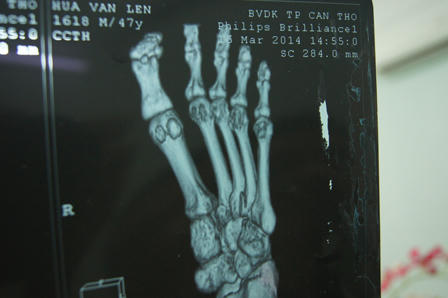

Tình trạng ông Lến lúc nhập viện: “Không đứng được bằng chân trái do đau, nhức đầu, sưng vùng thái dương phải, sưng vùng đỉnh giữa, bầm tím, sưng mặt lòng bàn chân trái, bầm tím mu chân trái từ ngón chân lan rộng đến cổ chân”. Kết quả chụp X-quang: “Gãy đầu gần xương bàn 4 bàn chân trái”.

Giấy chứng nhận thương tích số 363/CN-BVCT ngày 23/12/2013 của Bệnh viện Đa khoa TP.Cần Thơ ghi rõ: “Ông Hứa Văn Lến bị chấn thương đầu, gãy kín đầu gần xương bàn 4 chân trái, chấn thương khớp cổ bàn chân trái. Khi xuất viện, bàn chân trái giảm sưng đau nhưng vẫn còn bầm xanh lẫn bầm tím lan rộng”.

Sau khi ra viện, ông Lến làm đơn yêu cầu Cơ quan Cảnh sát Điều tra Công an huyện Kế Sách cho phép ông được trưng cầu giám định pháp y về thương tích. Ngày 3/1/2014, Trung tâm Pháp y Sóc Trăng có bản Kết luận giám định pháp y về thương tích số 06/TgT-PY ghi: “Bàn chân và cổ chân trái của ông Lến còn đau khi vận động, chụp X-quang thấy gãy xương bàn 4 bên trái đã liền cale”; tỉ lệ thương tật xác định là 11%”.

Ngày 14/4/2014, Phân viện Pháp y Quốc gia có bản Kết luận giám định pháp y về thương tích số 21/14/TgT. Bản kết luận này ghi: “Chụp X-quang bàn chân trái: không phát hiện gãy đầu gần ngón IV bàn chân trái”. Điều khó hiểu hơn là kết quả hội chẩn giữa Phân viện Pháp y với khoa X-quang Trung tâm y khoa Medic ngày 10/4/2014 lại cho rằng:

“Trên phim X-quang bàn chân trái chụp ngày 19/12/2013 tại Bệnh viện Đa khoa TP.Cần Thơ không thấy dấu hiệu gãy xương bàn ngón IV”. Căn cứ vào kết quả giám định này, Phân viện Pháp y kết luận: “Hiện tại không phát hiện di chứng do tổn thương vào thời điểm 15/12/2013. Sức khỏe bị giảm do thương tích gây nên hiện tại là 0%”.

Như vậy, cùng một phim chụp X-quang, trong khi phía bệnh viện chẩn đoán có gãy xương thì Phân viện Pháp y lại cho rằng không gãy? Ngày 16/3/2014, tức hai ngày sau khi có kết luận của Phân viện Pháp y, ông Lến tới Bệnh viện Đa khoa TP.Cần Thơ chụp X-quang lại bàn chân trái thì kết quả vẫn cho thấy ông bị gẫy đầu gần xương bàn 4 chân trái, đi lại vẫn còn đau. Thế nhưng kết quả giám định tại Phân viện Pháp y lại “đổi trắng thay đen” xác định là không gãy.